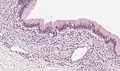

| Micrograph showing a mucinous cystadenoma of the ovary. H&E stain. | |

Mucinous cystadenoma is a benign cystic tumor lined by a mucinous epithelium. It is a type of cystic adenoma (cystadenoma).

Microscopy